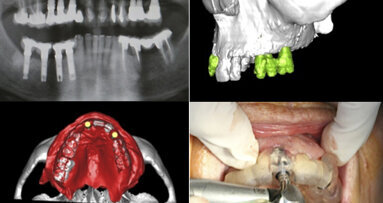

Sin duda, la implantología guiada por computadora para la planificación de la cirugía implantológica. En biomateriales, la aplicación de proteínas óseas morfogénicas en varios procedimientos de injertos. Y desde el punto de vista protésico, el uso generalizado de la tecnología CAD-CAM (Diseño Asistido por Ordenador/Fabricación Asistida por Ordenador) en pilares paciente-específicos elaborados de titanio o zirconio, que ofrecen una verdadera solución estética para muchos de nuestros pacientes.

En la Escuela de Odontología de Loma Linda University estamos muy emocionados ante las posibilidades de la tecnología Cone Beam en cirugía y restauraciones de implantes. A nivel de estéticá, seguimos explorando técnicas y procedimientos para mejorar y mantener la estética de las restauraciones de implantes. En injertos, estamos muy contentos de haber obtenido resultados positivos con las proteínas morfogénicas óseas en cirugía de implantes.

Sí, porque llegará a un nivel de precisión absoluta. Pero actualmente es importante reconocer el valor de los principios fundamentales de la cirugía de implantes dentales, que son la base de los tratamientos exitosos.

La tomografía axial computarizada (TAC) permite hacer una valoración exhaustiva de la anatomía del paciente y fabricar un dispositivo ...